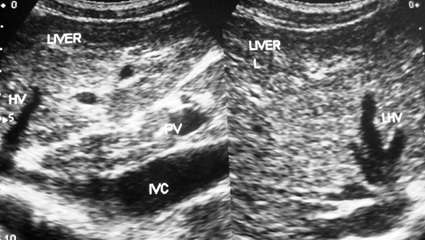

Figure 3a A young boy with CHB in replicative phase showing stenosis of a long segment of inferior vena cava filled with thrombus close to the site of hepatic vein. Distal segment is dilated and liver parenchyma shows features of cirrhosis. Middle hepatic vein is patent and dilated.

Figure 3b This patient with cirrhosis developed ascites from recurrence of acute exacerbation. The hepatic portion of inferior vena cava was filled with thrombophlebitis. Intra-hepatic veins are thrombosed with intimal thickening. There is a layer of peri-hepatitis around the liver and gall bladder wall is thick. Patient responded to medical treatment.

Figure 3 Development of liver cirrhosis in hepatic vena cava syndrome.

HVCS induced liver cirrhosis at an early stage showed some characteristic US/CD features that make it clinically recognizable.42 In liver cirrhosis due to other causes hepatic veins are often attenuated and not visible. HVCS induced cirrhosis may show dilated hepatic veins with evidence of HVOO, and occasional other findings as intimal thickening of intra-hepatic veins, edematous or thick gallbladder wall, and presence of calcified foci in the liver and a thick layer of peri-hepatitis around the liver due to past ascites with bacterial peritonitis (Figure 3b). Re-occurrence of jaundice or transaminases elevation or ascites in HVCS induced cirrhosis is frequently due to acute exacerbation and not due to hepatic decompensation (Figure 3b).42 Splenomegaly and development of esophageal varices are regarded as important features of advanced cirrhosis with portal hypertension in the West. HVCS patients with recurrent acute exacerbations developed splenomegaly with hematological features of hypersplenism long before development of cirrhosis, as was seen in some of the patients reported here. Sinusoidal hypertension during acute exacerbation resulted in backflow in portal vein resulting in portal hypertension with mild esophageal varices and dilatation of veins in the splenic hilum. Such patients with thrombocytopenia may have mild episodes of self-limiting variceal bleeding during acute exacerbations. Some rarely also develop hepatic encephalopathy before the development of liver cirrhosis due to bypassing the liver by splanchnic blood and returning to systemic circulation through dilated collaterals around the spleen. Development of these features should not be taken as signs of hepatic decompensation and an indication for liver transplantation in HVCS induced cirrhosis.